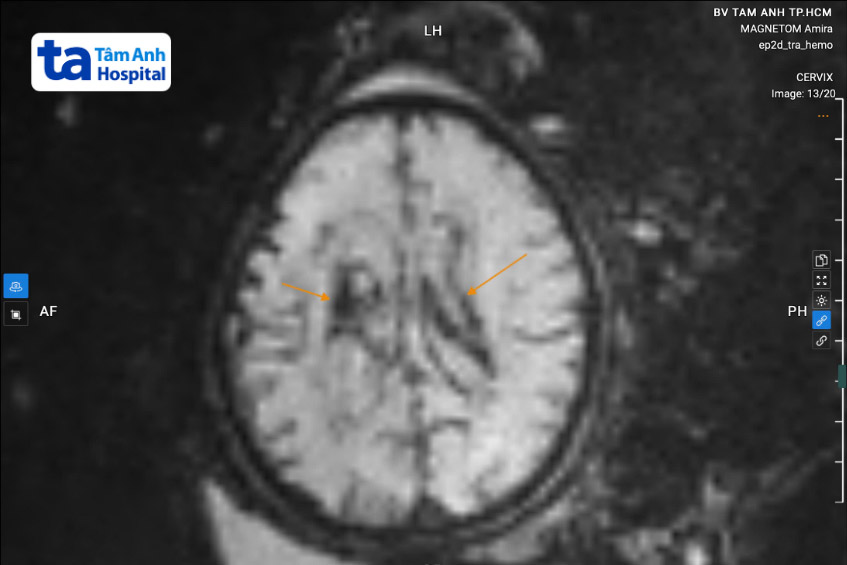

TS.BS Nguyễn Hoàng Long, Phó giám đốc Trung tâm Y học bào thai, cho biết hình ảnh MRI gợi ý thai nhi xuất huyết não độ 4 theo phân loại Papile, tụ máu ở xoang ngang và nhu mô não, giãn não thất mức độ trung bình (12-15 mm).

Chị Nhâm mang thai tuần 35, chụp MRI phát hiện thai nhi xuất huyết não độ 4, tiên lượng nặng.